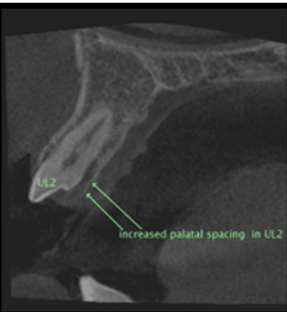

CBCT Imaging & Diagnostics

We are qualified to prescribe and review 3D CBCT imaging. This provides precise 3D views of root of teeth for accurate diagnosis and planning—minimising guesswork and improving outcomes.

- High-resolution 3D visualisation

- Targeted field of view to reduce exposure

- Improved detection of complex anatomy